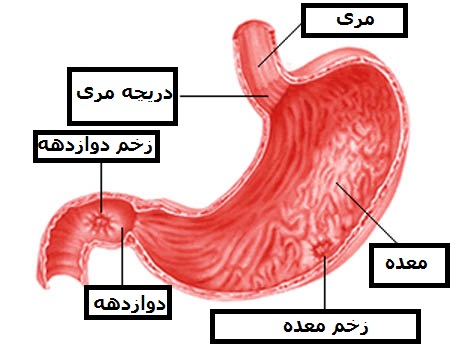

قیمت: 40٬000 تومان - دسته بندی فایل: پاورپوینتپاورپوینت درباره زخم پپتیک peptic ulcer

پاورپوینت درباره زخم پپتیک peptic ulcer